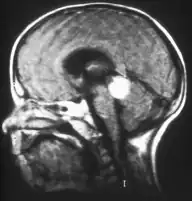

-

Drawing of a large retinoblastoma -

Aspect of trilateral retinoblastoma on MRI -